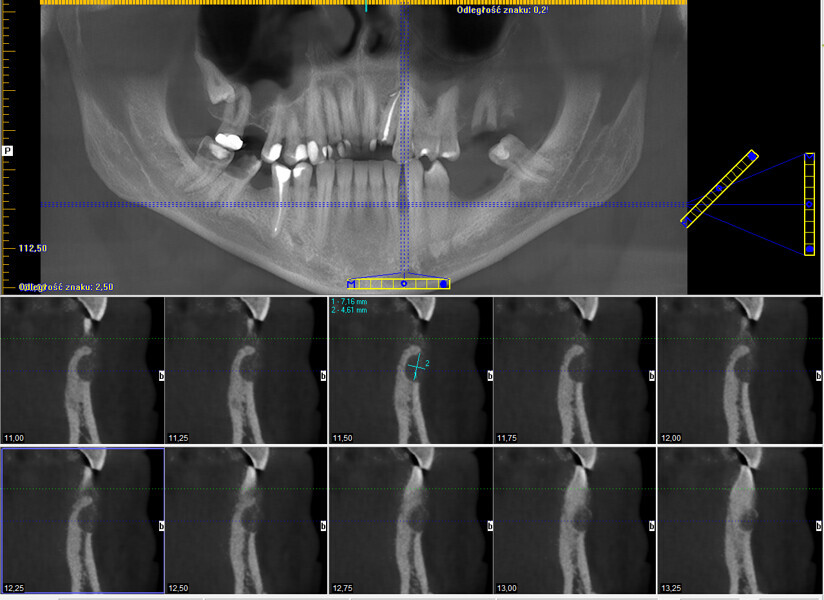

Śródkostna postać torbieli naskórkowej zlokalizowana w żuchwie – opis przypadku